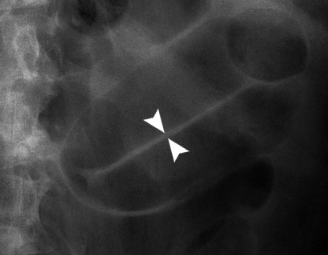

What pathology is indicated in this AXR? [1]

A

False Rigler’s/double wall sign

* Be careful not to mistake the gas within two adjacent bowel segments for Rigler’s sign.

* Gas seen on both sides of the bowel wall is contained within adjacent bowel

* There are no black triangles or sharp angles on the outside of the bowel wall